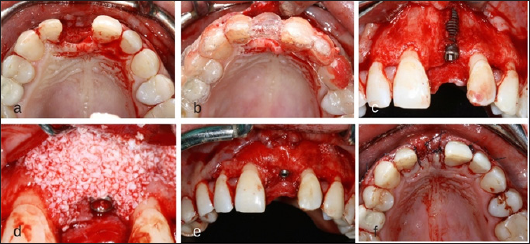

After 6 months healing impressions were taken to confection a diagnostic wax-up, and then a radiological splint. After the CBCT Scan, implant planning was performed with MGuide® Software (MIS Implants Technologies, Israel) (Figure 3). Under local anesthesia a 4 per 10 mm. Astra TX® implant (Astra Tech®, Densply, Sweden) was placed, due to the poor availability of bone an implant dehiscence was created in the buccal area, simultaneous bone regeneration was performed with Xenograft (Bio-Oss®, Geistlich Biomaterials, Parma, USA) and membrane (Mem-Lok®, Bihorizons, Birmingham, USA) [7]. As high implant primary stability was not achieved patient continued with the Maryland Bridge during the healing period (Figure 4). Six months after implant placement, a connective tissue graft harvested from tuberosity was performed to improve soft tissue contour around implant. An atraumatic second surgery [8] was performed using the provisional Maryland Bridge that the patient wears during healing period by the progressive addition of filling material.

Figure 5: (a) Occlusal View of the Crest Before the Implant Placement Surgery; (c) Surgical Stent for the Three-Dimensional (3d) Implant Placement; (c) Situation Of The Implant After Correct 3d Position; (d-e) Contour Augmentation with Desproteinized Bovine Bone Mineral And Covered with a Resorbable Collagen Membrane; (f) The Surgery was Completed by Tension-Free Primary Wound Closure.